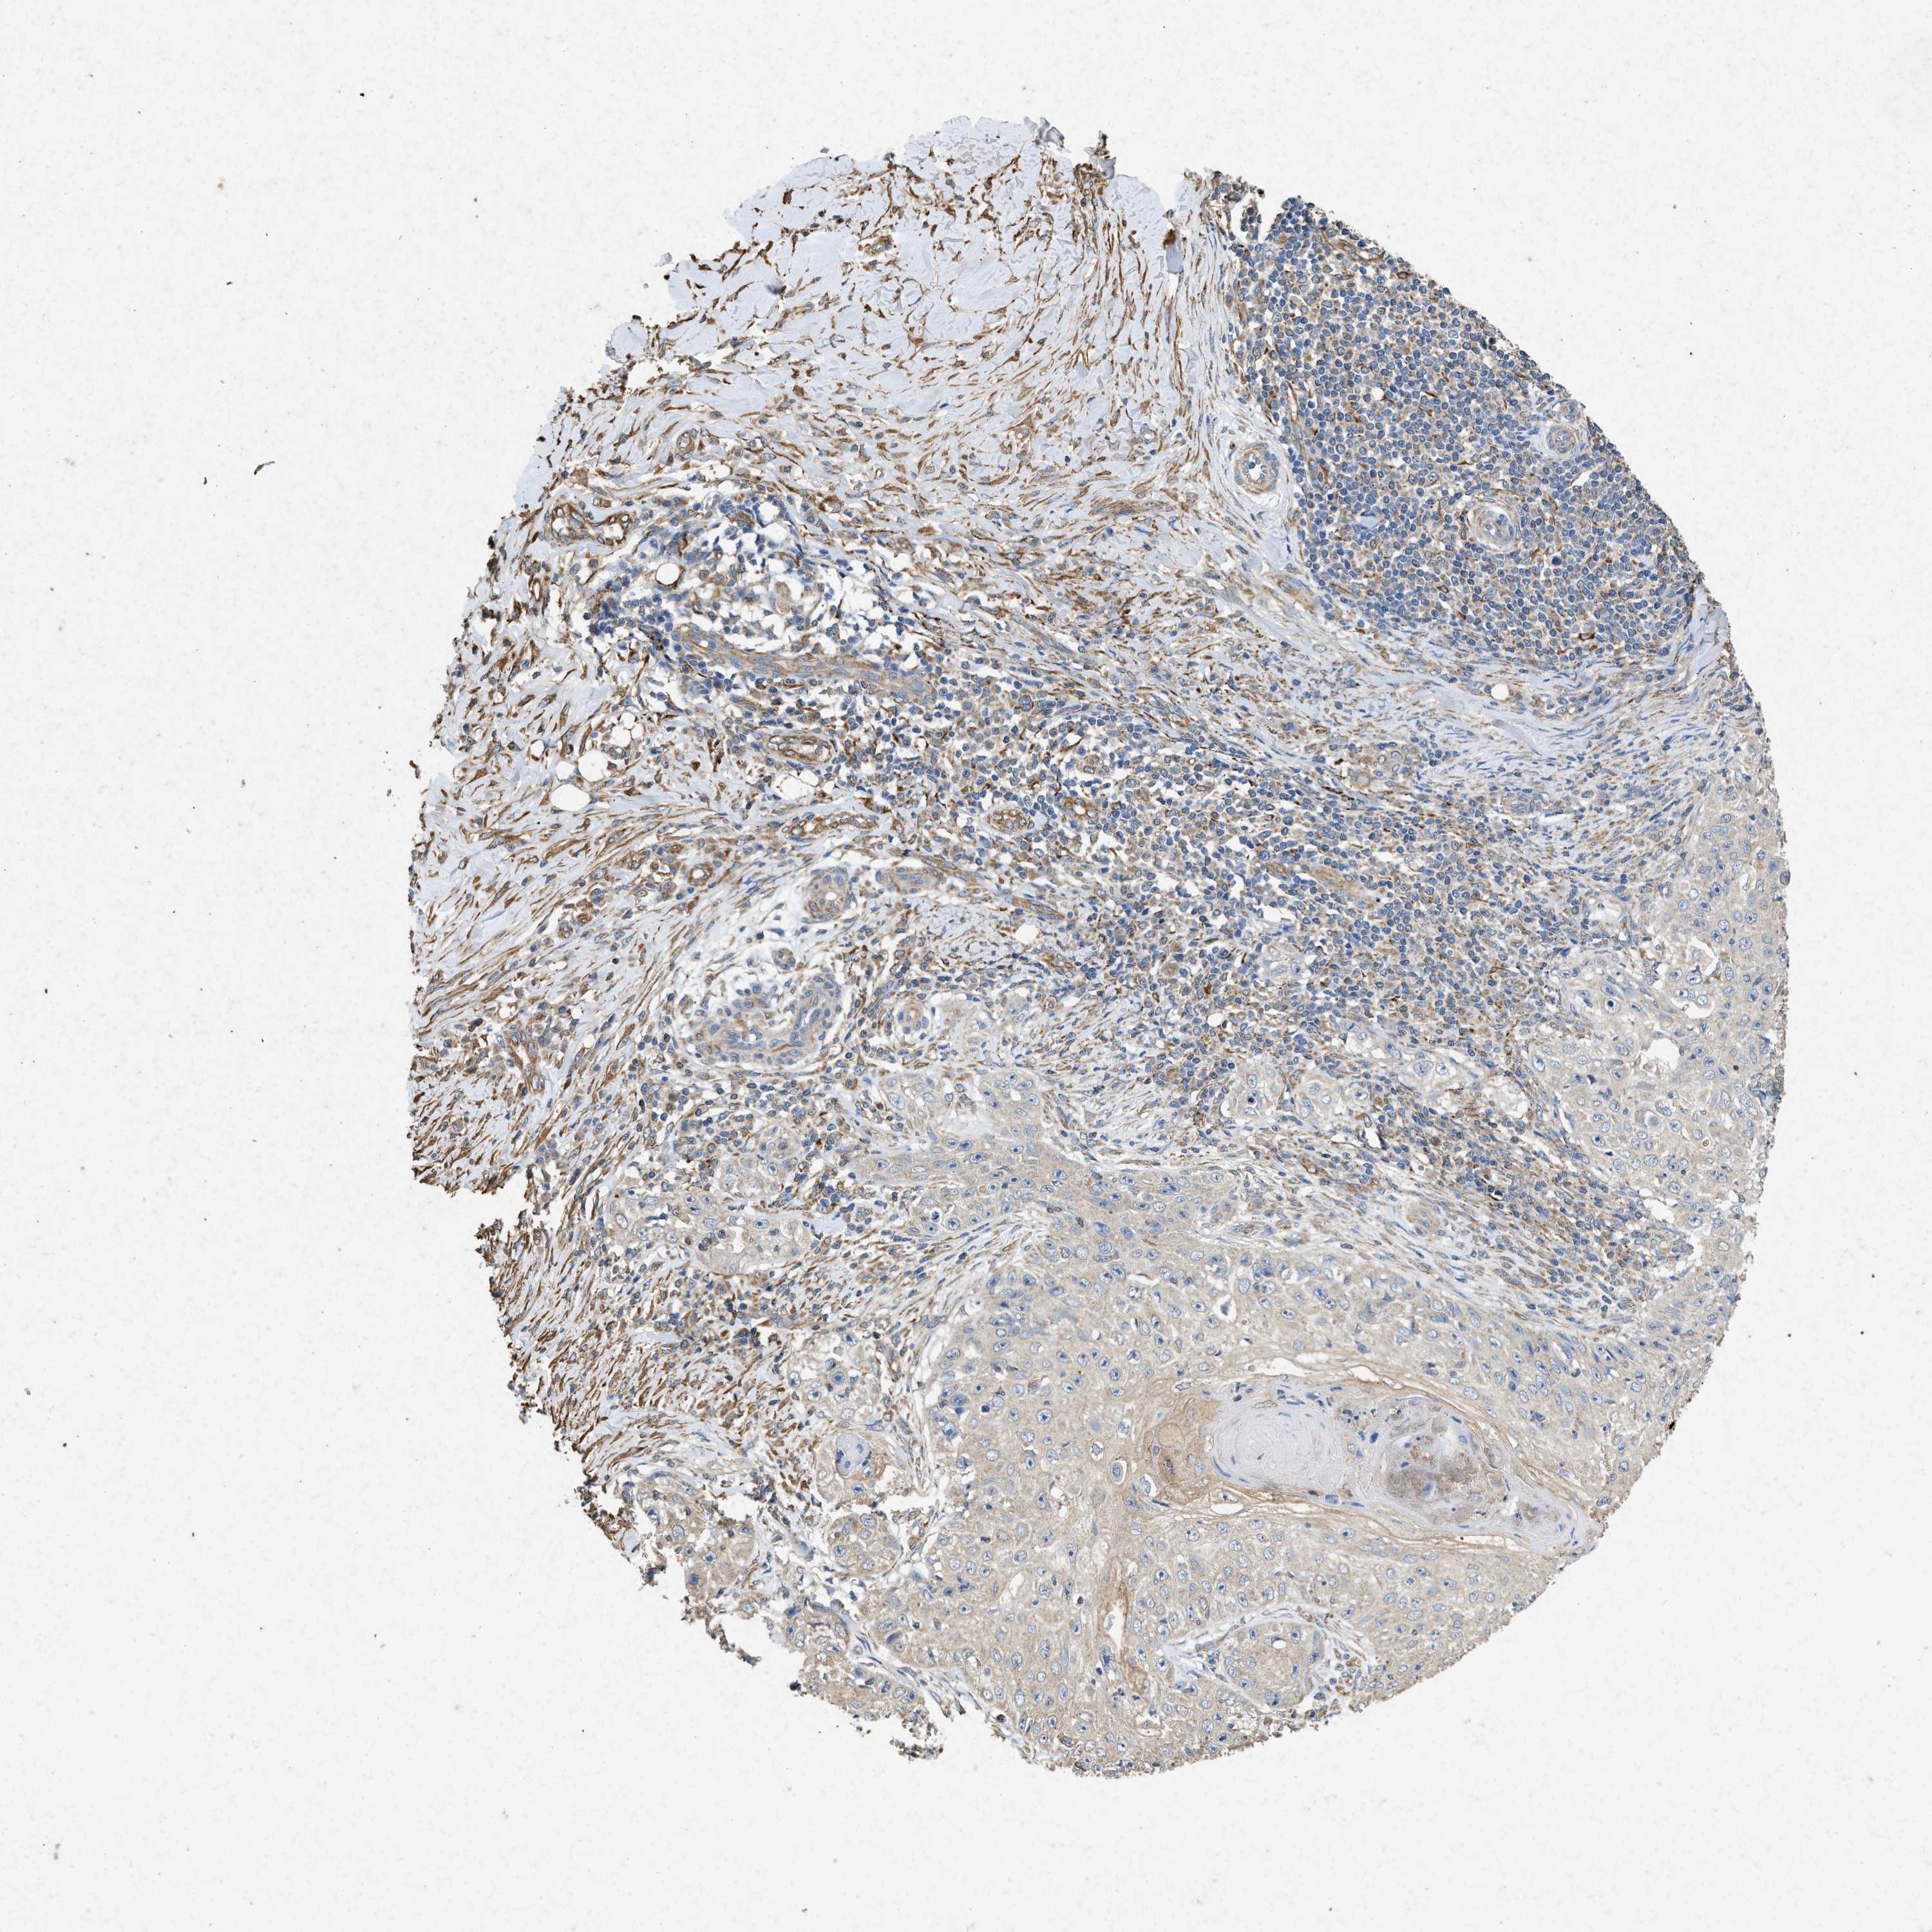

SKIN CANCER - Protein expressioni

A mouse-over function shows sample information and annotation data. Click on an image to view it in a full screen mode. Samples can be filtered based on level of antibody staining by selecting one or several of the following categories: high, medium, low and not detected. The assay and annotation is described here.

Note that samples used for immunohistochemistry by the Human Protein Atlas do not correspond to samples in the TCGA dataset.

Antibody stainingi

Antibody staining in the annotated cell types in the current human tissue is reported as not detected, low, medium, or high, based on conventional immunohistochemistry profiling in selected tissues. This score is based on the combination of the staining intensity and fraction of stained cells.

Each image is clickable and will lead to virtual microscopy that enables deeper exploration of all samples and also displays staining intensity scores, fraction scores and subcellular localization as well as patient and tissue information for each sample.

Antibody HPA015786

Staining

Squamous cell carcinoma, NOS